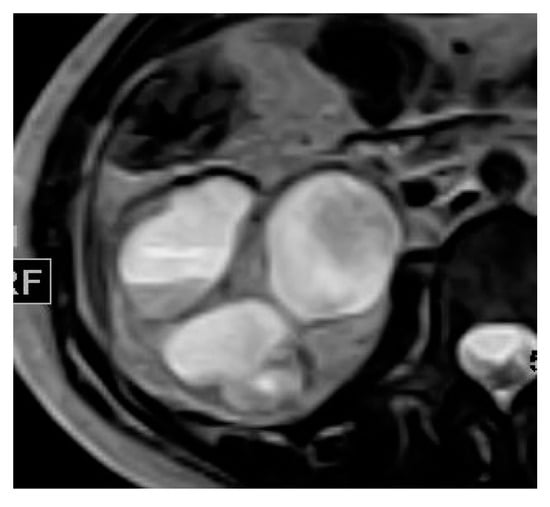

2.3. Pyonephrosis

| Pyonephrosis | Dilated thick-walled hyperenhancing collecting system, distended with high attenuation pus-filled fluid, fluid—fluid layering at T2WI, and thinning of the renal cortex. |